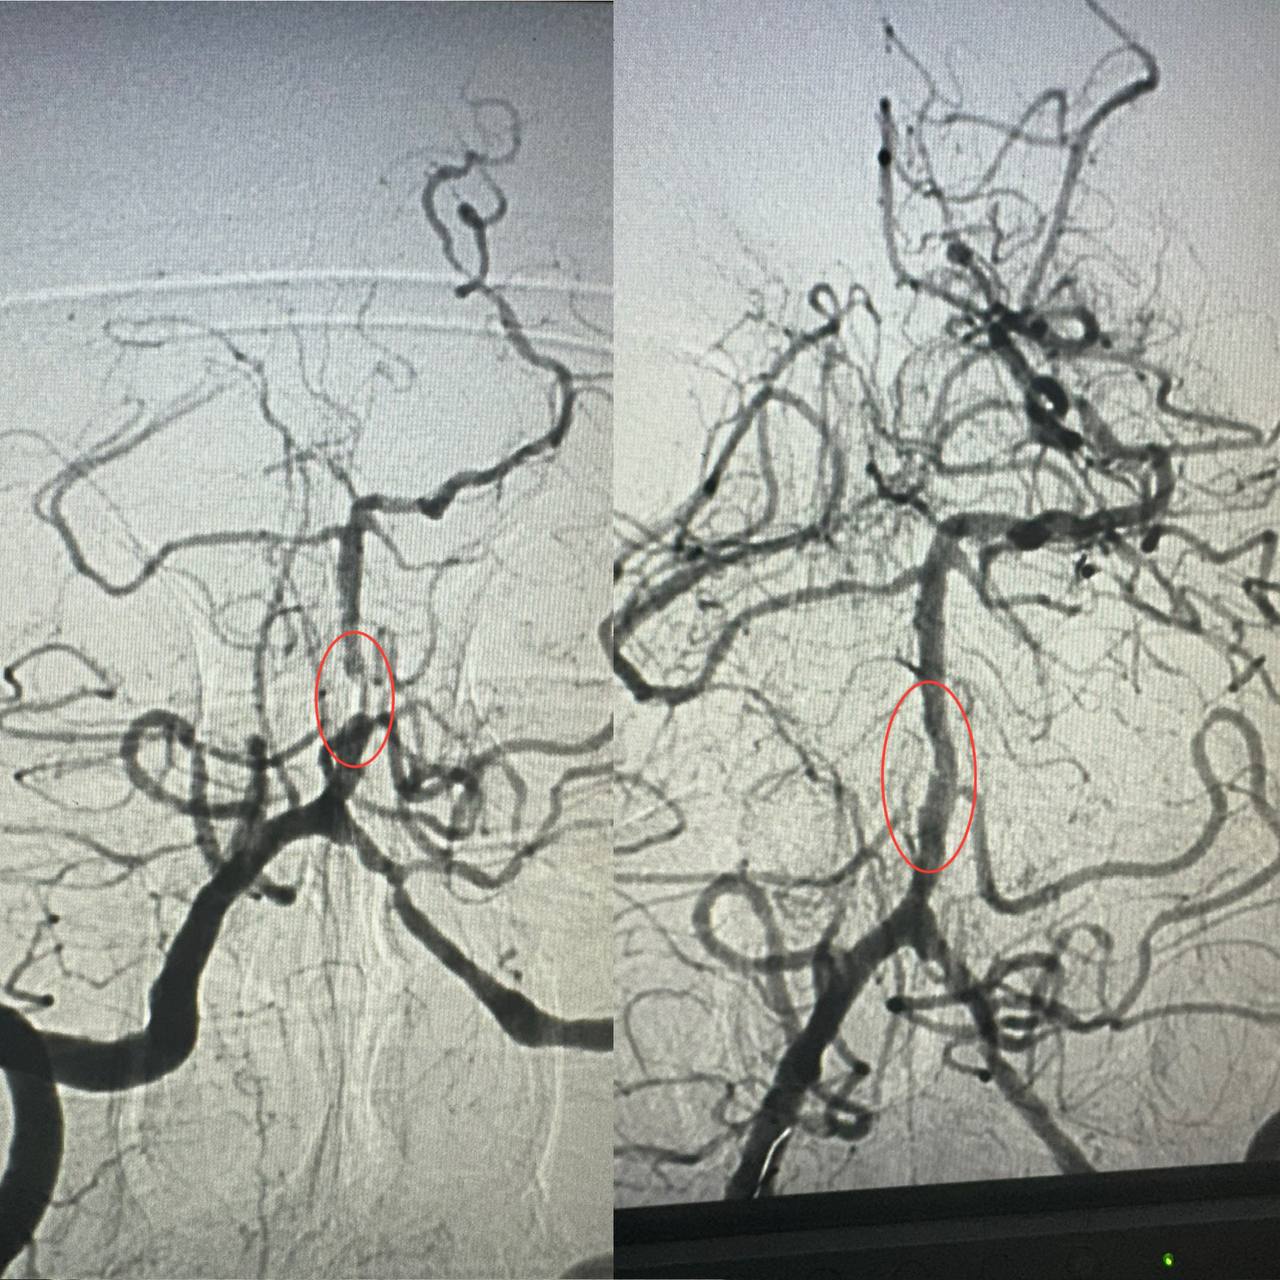

Як розповів завідувач рентгенендоваскулярним блоком лікарні Олександр Скрипка, це був один з найскладніших випадків – ураження стовбурової частини мозку. Базилярна артерія була майже повністю закрита атеросклеротичною бляшкою. Такі інсульти належать до найбільш небезпечних.

Фахівці прийняли рішення провести ангіопластику артерії. Десята лікарня має досвід такої методики лікування в кардіології при атеросклерозі коронарних судин, але застосування її для мозкових судин – це іноваційна технологія для України.